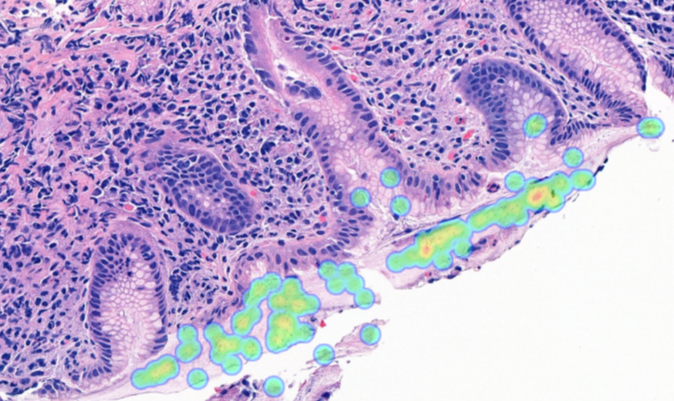

Manual screening for gastric carcinoma and Helicobacter pylori (H. pylori) is time-consuming and challenging. Subtle tumor foci and low bacterial density are subject to interobserver variability and workload pressure.

Aiforia® Gastric Suite uses AI to analyze digitized whole slide images to address these challenges. By highlighting suspicious areas directly on the slide, it enables efficient review while ensuring the pathologist remains in full control of interpretation and reporting.